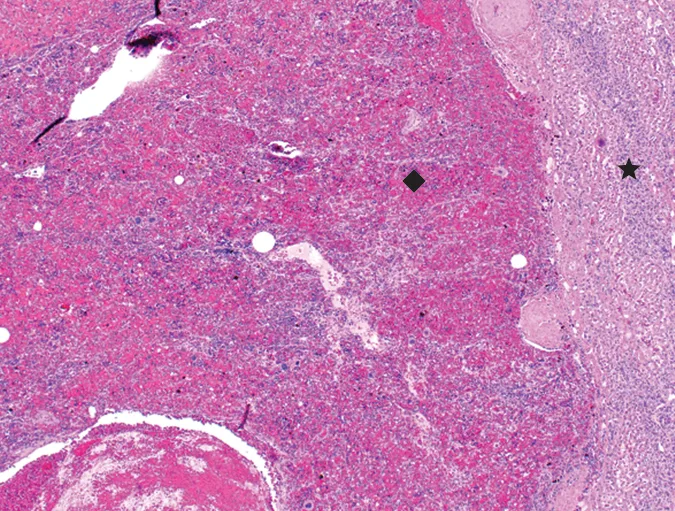

Ultrasonographic appearance of 10.5-cm cavitated mass in the right liver lobe near the porta hepatis on recheck examination 5 months postoperatively. The mass was suspected to be a recurrence of hepatic splenosis, and cytology was consistent with extramedullary hematopoiesis; however, biopsies for histopathology were not pursued. Area of mass demonstrated by arrows

Abdominal radiographs taken 3 months postoperatively were unremarkable. Sophie experienced a brief episode of vomiting 4 months postoperatively, and packed cell volume (PCV) was 34%; however, ultrasonography was not performed, and she recovered without therapy. Five months postoperatively, she was clinically normal, and a routine recheck identified a PCV of 39%. Ultrasonography at this time identified a 10.5-cm cavitated mass in the right liver near the porta hepatis (Figure 4) and an 8.6-cm hepatic mass with similar appearance to the presurgical ultrasound findings; hemoabdomen was not present. Although recurrence of hepatic splenosis was suspected, hemangiosarcoma or other neoplasia could not be ruled out. Cytology revealed extramedullary hematopoiesis.